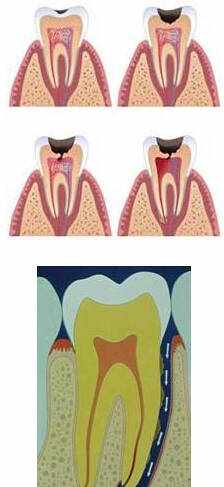

龋齿的发展

1

白斑

牙垢沉积在牙齿表面,牙齿表面珐琅质被牙垢中的细菌消化糖后,排泄出来的酸溶解,就发生脱矿了。

牙齿中的钙减少了,色泽就变成白粉笔色(白琧)感觉了。

2

釉质龋

脱矿没有及时修复,牙齿表面开始缺损,就成为我们说的蛀牙、牙洞了。

早期的龋齿患者是没有感觉的,因此容易出现拖延,导致错过治疗的最佳时期。

3

牙本质或牙骨质龋

随着龋坏的发展,逐渐出现喝冷热水或者进食时敏感不适。

4

深龋

此时如果不及时治疗龋坏,将继续向深层牙体组织发展,就会出现遇冷遇热疼痛,之后形成明显龋洞。

当有食物进入龋洞后常导致患牙疼痛,此时已发展为深龋,换言之,龋洞已经很深,洞底与牙神经之间的距离已经非常近。

5

牙髓炎

如果此时依然没有及时治疗,龋坏里的细菌会入侵牙神经。

这会导致:牙神经发炎,牙齿出现自发疼痛,并且逐渐加剧,重者夜间睡眠受到影响,需要口含冷水才能使疼痛稍有缓解。

此时,疾病的名称为牙髓炎。

6

根尖周炎

疾病至此,如果患者仍旧未及时治疗,牙神经内的细菌会继续向深层入侵,到达牙根的根尖区域,此时称为根尖周炎。

患牙的自发疼痛减弱,牙根区域出现跳痛,牙齿咬合疼痛,并出现患牙伸长浮起的感觉。

根管治疗的过程:(见图)

根管治疗的过程:(见图)